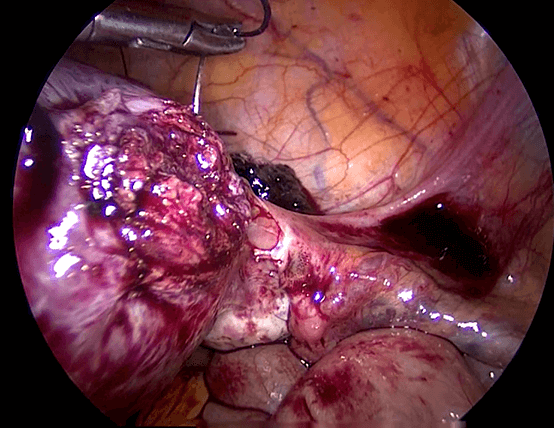

Saat kehamilan ektopik berada di daerah kornu rahim ( Gambar 7.4 ), maka kehamilan biasanya didiagnosis masih lama lagi. Kehamilan kornu jauh lebih sulit untuk dieksisi secara laparoskopi karena ukuranya lebih besar dan dapat berdarah dengan menyebar luas. Teknik ini melibatakan suntikan vasopressin disekitar kornu kehamilan ektopik dan penempatan jahitan purse string di sekitarnya. Kemudian sayatan dibuat untuk enukleasi kehamilan ektopik. kerusakan kemudian dijahit. Pada kehamilan kornu yang besar, bagian dari rahim harus diangkat bersama-sama dengan tuba. Pada kasus- kasus yang sulit, laparotomi mungkin diperlukan.

Reseksi laparoskopi kornu kehamilan ektopik

Pada tahun 2009 nyonya UDS datang mengunjungi saya , dia telah menikah 3 tahun dan dia tidak bisa hamil. Histerosalpingogram yang dilakukan di rumah sakit yang lain menunjukkan kedua tubanya tersumbat / terblokir. Dia menjalani laparoskopi , dan laparoskopi menunjukkan ukuran rahim yang normal. Kedua tuba nya normal dan dipatenkan setelah insulfasi tuba dilakukan dibawah tekanan. Dia hamil secara spontan 2 bulan setelah menjalani laparoskopi namun sayangnya kehamilan berakhir dengan aborsi yang terlewatkan. Dia telah menjalani evakuasi hasil konseptus. Pasca operasi , keadaan dia baik-baik saja akan tetapi tidak dapat hamil. Dia telah diberikan beberapa siklus klomifen sitrat namun tanpa membuahkan hasil. Pada tahun 2011, dia menjalani siklus inseminasi intrauterin setelah diberikan suntikan hormon perangsang folikel ( FSH ). Setelah prosedur dilakukan , dia hamil akan tetapi sayangnya kehamilan itu adalah kehamilan ektopik. Dia menjalani reseksi laparoskopi kornu kanan kehamilan ektopik di tahun 2011 ( Gambar 26.7 – 26.11 ) ( simak video 26.3 ). Pasca operasi di tahun 2013 dia menjalani histerosalpingografi dan menunjukkan bahwa tuba kiri tidak paten. Dia dapat hamil setelah menjalani IVF.

Kornu kehamilan ektopik tidaklah umum. Biasanya didiagnosisnya terlambat karena pasien dengan kondisi seperti ini tidak memliki banyak gejala-gejala. Pecahnya kehamilan ektopik pada kornu dapat menyebabkan pendarahan yang berlebihan. Pada pasien ini diagnosis dilakukan lebih awal karena dia menjalani IUI dan berada dalam pengawasan secara teratur. Eksisi telah dilakukan dengan berhasil secara laparoskopi.